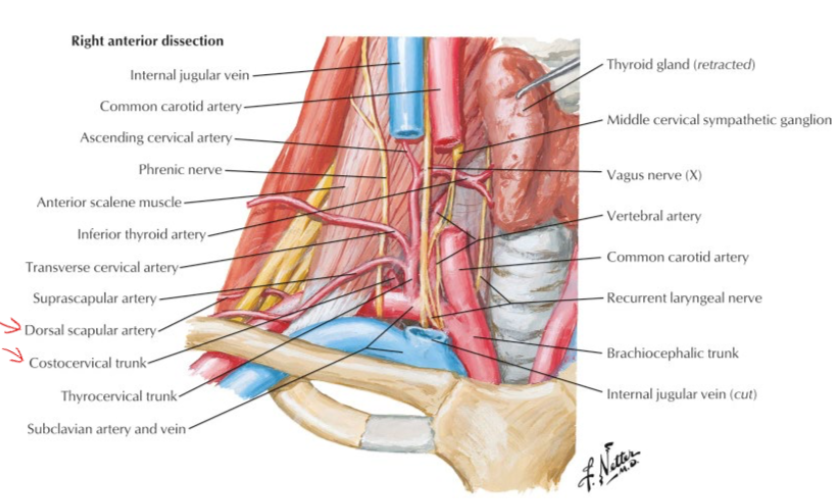

Subclavian a.

Info

Scalene m.

ant.,mid. scalene insertion at rib 1

post. scalene insertion at rib 2

Thyrocervical trunk

Axillary a.

Common carotid

SCM血液

上1/3

中1/3

- Sup. thyroid a.

- Ext. carotid a.

下1/3

- suprascapular a. (>80%)

subclavian vein 在ant. scalene m. 上方

CN X

Structure

- common carotid a. 外側,蓋在 thyrocervical trunk 上

- recurrent laryngeal n.沿 tracheoesophageal groove 攀升(就是食道和氣管中間),接觸 medial thyroid gland,向內鑽到 inf. constrictor,進入 larynx,同時支配感覺與運動

recurrent laryngeal n.

- left: arch of aorta

- right: Subclavian a.